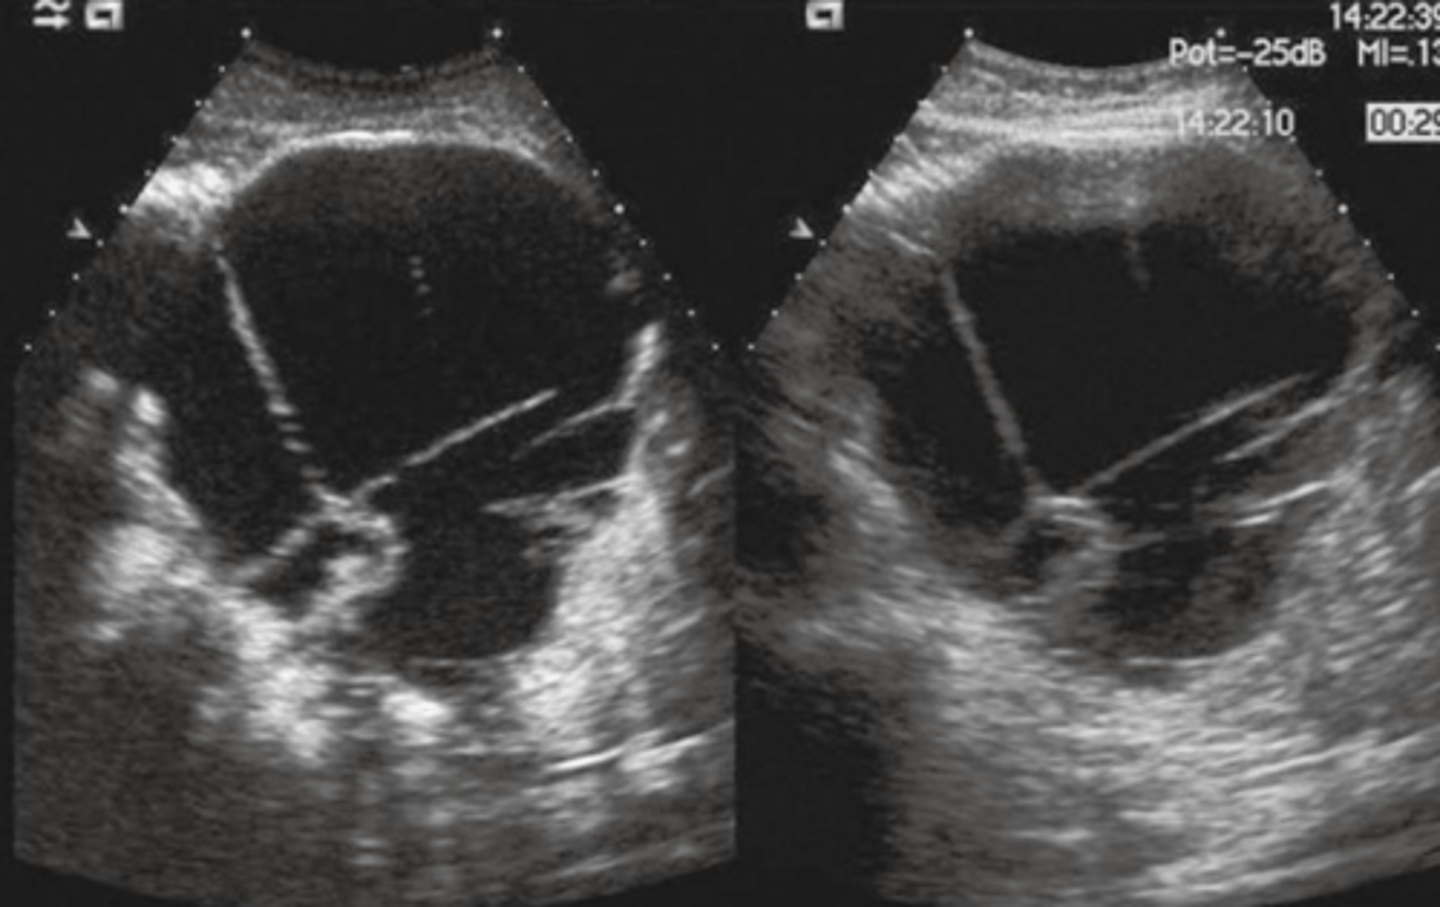

Carcinoma of Pancreas Sonographic Appearance

-80% are focal lesions

-loss of normal pancreatic parenchymal pattern

-irregular, nodular border

-localized change in echo texture

-gland enlarges at mass site

-henerally hypoechoic

-CBD, CHDs and pancreatic ducts may be dilated (courvoisier's)

-normal vascular landmarks may be obliterated or displaced (compressed IVC, spleen enlarged due to cmopression of SPLV)

-metastases to surrounding organs (liver, adrenal, GB, lymph nodes)

-ascites

Carcinoma of Pancreas